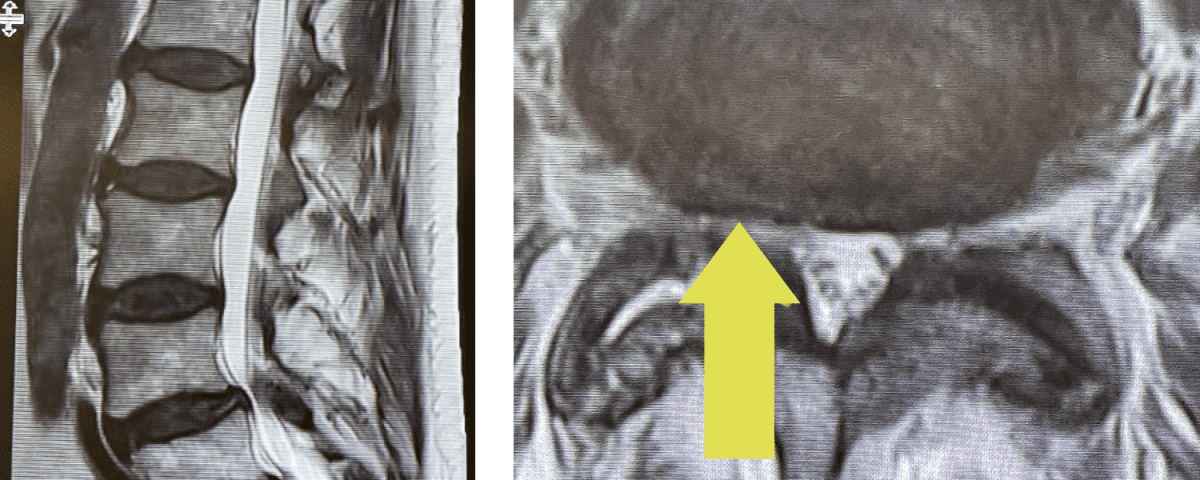

Fig 3: Intraoperative lumbar fluoroscopic lateral and AP images demonstrating good screw placement in performing an L4-5 fusion.

During the surgery we encountered the “cyst” as it was coming from inside or medial joint space between the two bony processes that make up the facet joint itself, like two puzzle pieces that fit together with a synovial-lined space that can for a degenerative synovial cyst. The cyst is like a pimple and actually is quite satisfying to pop and release the material that looks like curd as it is rarely liquid. Because of the consistency and the location, they are not really able to be aspirated or found. After we did what we set out to do which was to make the nerve sac without any pressure as well as the L5 nerve roots, which are most affected at this level. We performed a fusion with two titanium screws in L4 and two in L5, which were connected by rods that were bent or lordosed (Fig 3). They are easy to put in and serve the purpose of connecting the two levels to prevent any relative motion or translation of L4 on L5. This also most importantly prevents the body from signaling the spine to make arthritis to attempt to auto stabilize itself. After the surgery the patient had relief of his right leg pain and had an uneventful postoperative course.